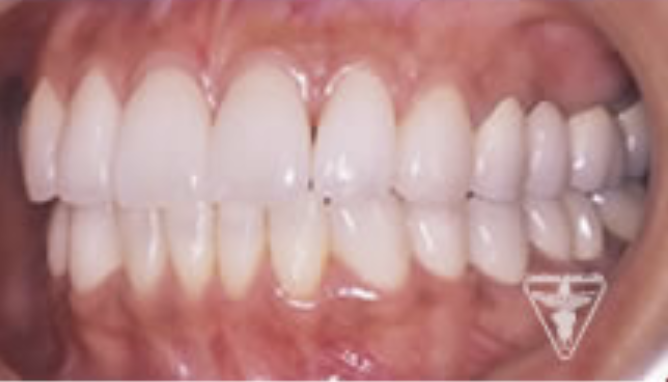

治療後

顎のずれを改善し、上下のかみ合わせの関係を理想的にして筋肉や関節の緊張が取れ、穏やかな表情に変られました。「良く噛めるようになった。」と評価をいただきました。